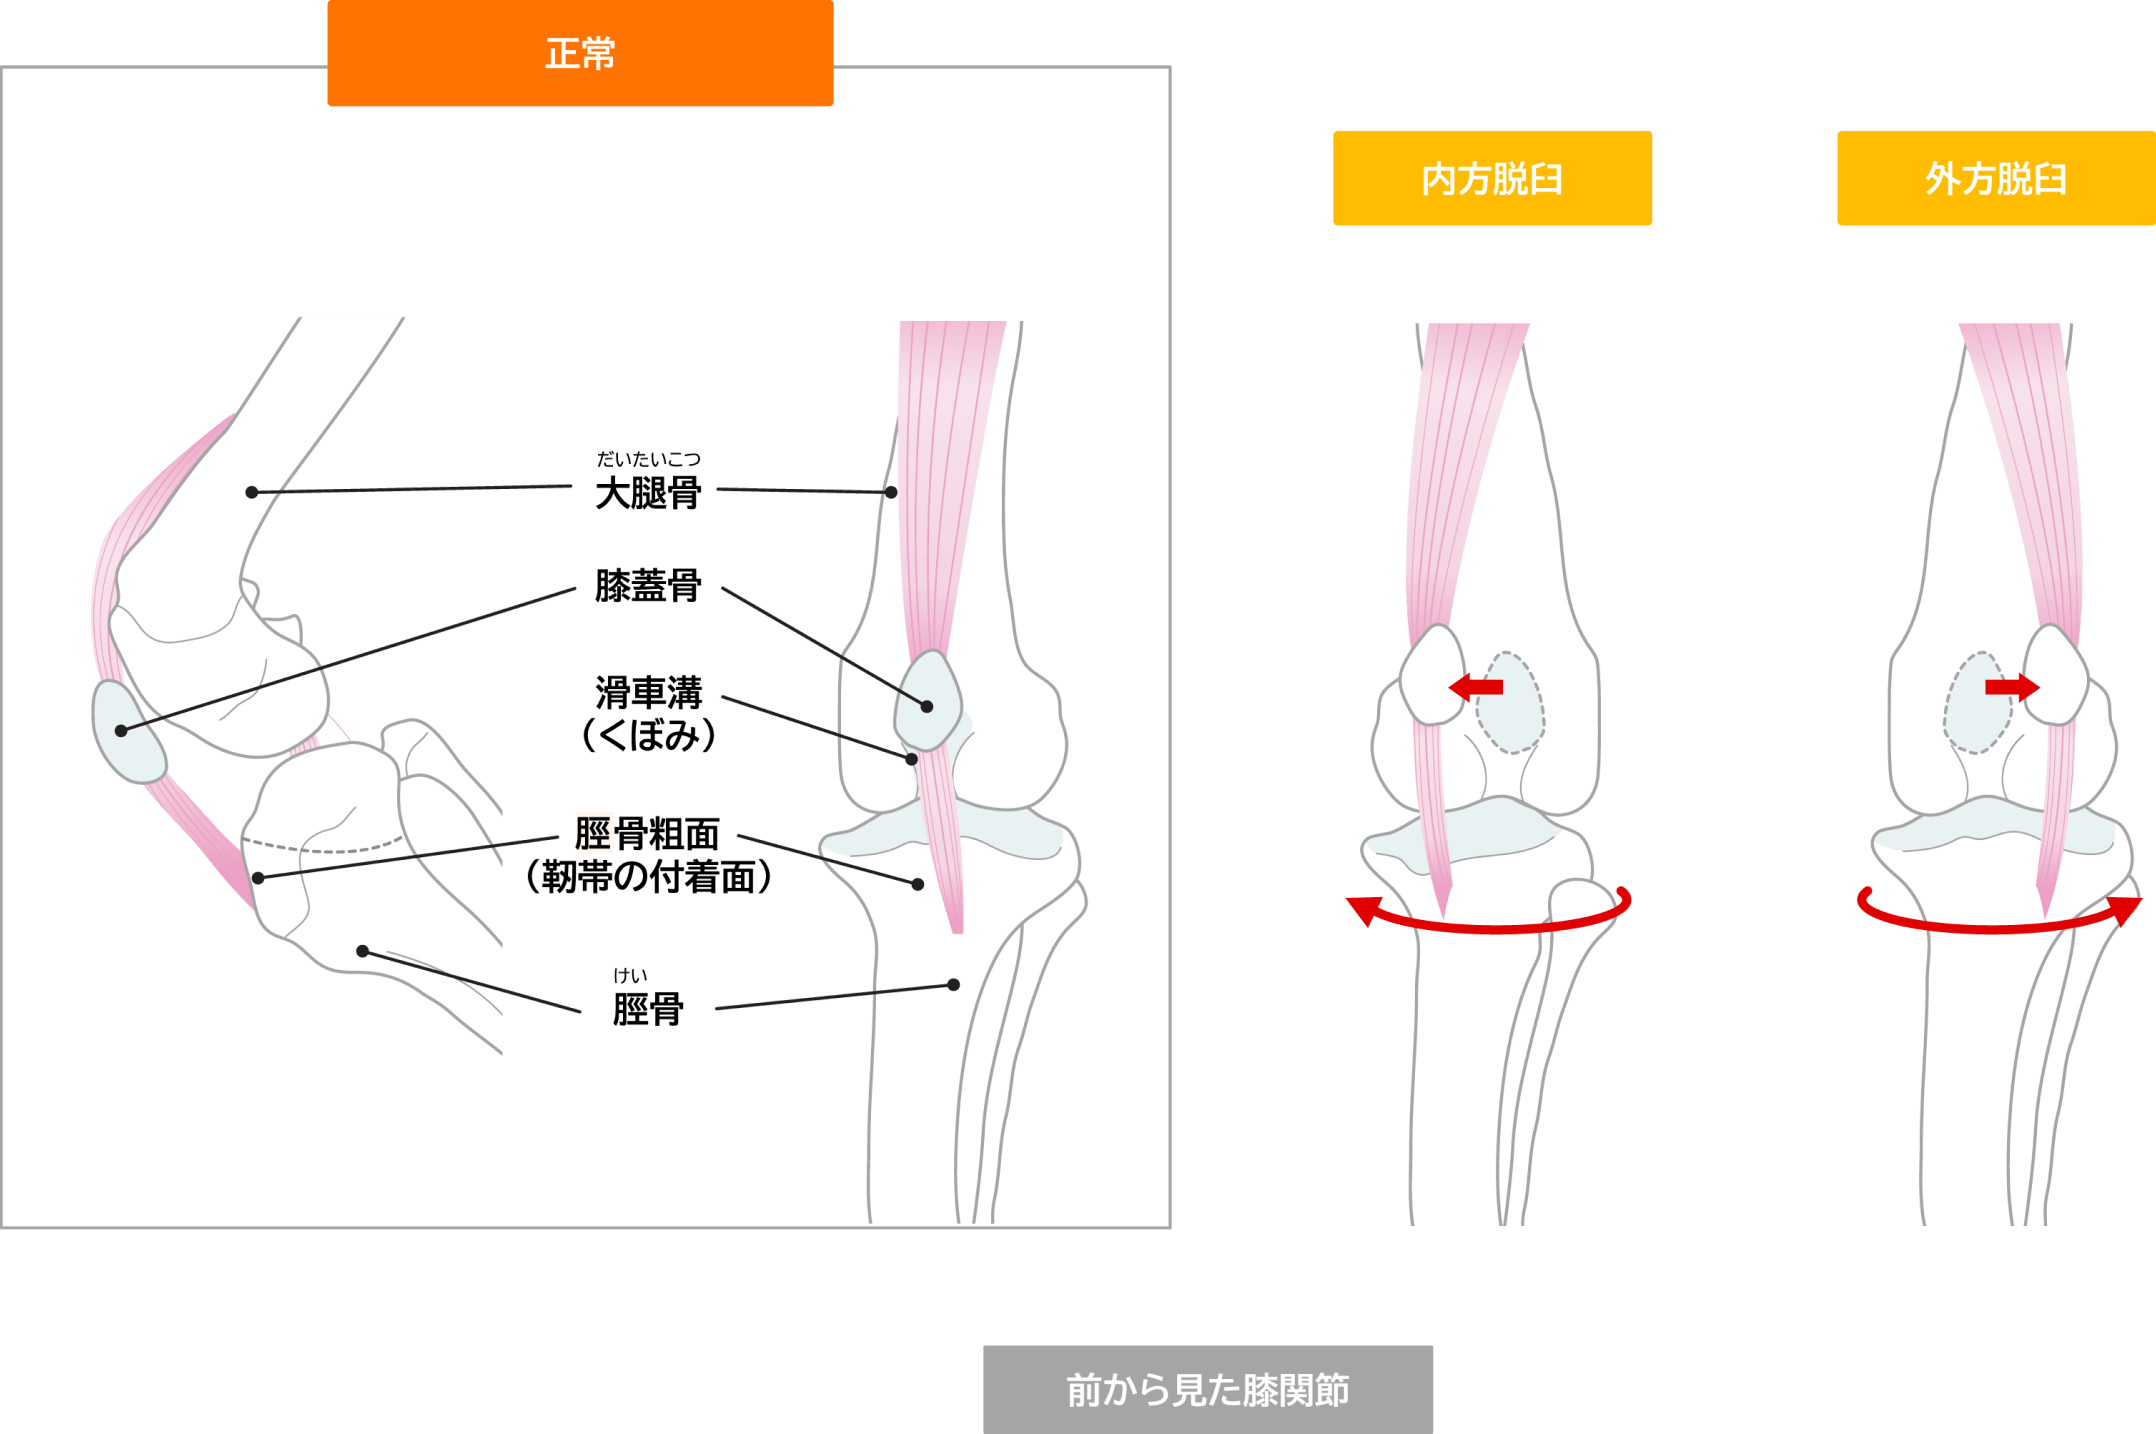

膝蓋骨脱臼とは

膝蓋骨脱臼は、犬によく見られる整形外科的問題の一つです。正常な膝関節では、膝蓋骨(膝のお皿)が大腿骨の滑車溝と呼ばれる溝の中をスムーズに動くことで、膝の曲げ伸ばしが可能になります。しかし、膝蓋骨脱臼では、この膝蓋骨が本来あるべき位置から外れてしまいます。

膝蓋骨が脱臼する4つの理由

• 大腿骨の滑車溝が浅すぎる

• 大腿四頭筋の発達不全

• 骨の捻れや湾曲

• 遺伝的要因(特に小型犬種に多い)

グレードについて

膝蓋骨脱臼の重症度は、一般的に以下の4段階で分類されます。

グレード1 グレード2(手術適応) グレード3 グレード4

症状 自然に脱臼することはまれで、手で脱臼させても元通り 自然と脱臼することもあり手で整復が必要。

軽度の骨の捻転・湾曲がある

常に脱臼していて手で修復できるがすぐに脱臼する。

骨の異常だけでなく、周囲の軟部組織の異常もできる

常に脱臼していて、手で整復できない。

歩く事もままならない事がある

重要なのは、グレード2の段階でも、飼い主が気づかないことが多いという点です。

定期的な獣医師の検診が早期発見・早期治療につながります。

滑車溝形成術

大腿骨の滑車溝を深くすることで、膝蓋骨が安定して動けるようにします。単に溝を削るだけでなく、関節軟骨を温存する技術も用いられ、術後の関節機能の維持を図ります。

外側支帯縫縮術

膝関節を包む組織(関節包)を調整します。内側に脱臼する場合は外側を、外側に脱臼する場合は内側を縫い縮めることで、膝蓋骨を正常な位置に引き戻します。

脛骨粗面転位術

脛骨の上部(脛骨粗面)を切り離し、適切な位置に移動させて固定します。これにより、膝蓋靭帯の付着部位を調整し、膝蓋骨にかかる力の方向を正常化します。

これらの手術法は、個々の症例の状態に応じて、単独または組み合わせて実施されます。術後は適切なリハビリテーションが重要で、専門的なケアにより良好な回復が期待できます。